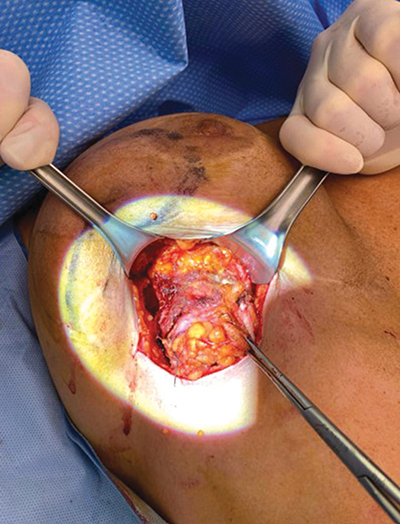

Silicone gel-filled breast implants are widely used for breast augmentation and reconstruction after mastectomy. However, there are some known complications associated with silicone implants: Leakage and migration of silicone particles from the implant cause a granulomatous reaction. Granulomas may present as masses with features of malignancy on breast MRI. We present a case of a giant breast siliconoma in a woman who had undergone reconstruction with breast prostheses, which were surgically removed because of rupture 8 years ago. Teaching point: Despite increasingly efficient diagnostic tools, siliconoma diagnosis remains challenging.

硅凝胶填充乳房假体广泛用于乳房切除术后的隆胸和重建。不过,硅胶假体也有一些已知的并发症:硅胶微粒从植入物中渗漏和迁移会引起肉芽肿反应。肉芽肿在乳腺核磁共振成像中可能表现为具有恶性肿瘤特征的肿块。我们介绍了一例巨大乳腺硅胶瘤病例,患者曾接受过乳房假体重建手术,8 年前因假体破裂而被手术取出。教学要点:尽管诊断工具越来越有效,但硅胶瘤的诊断仍然具有挑战性。